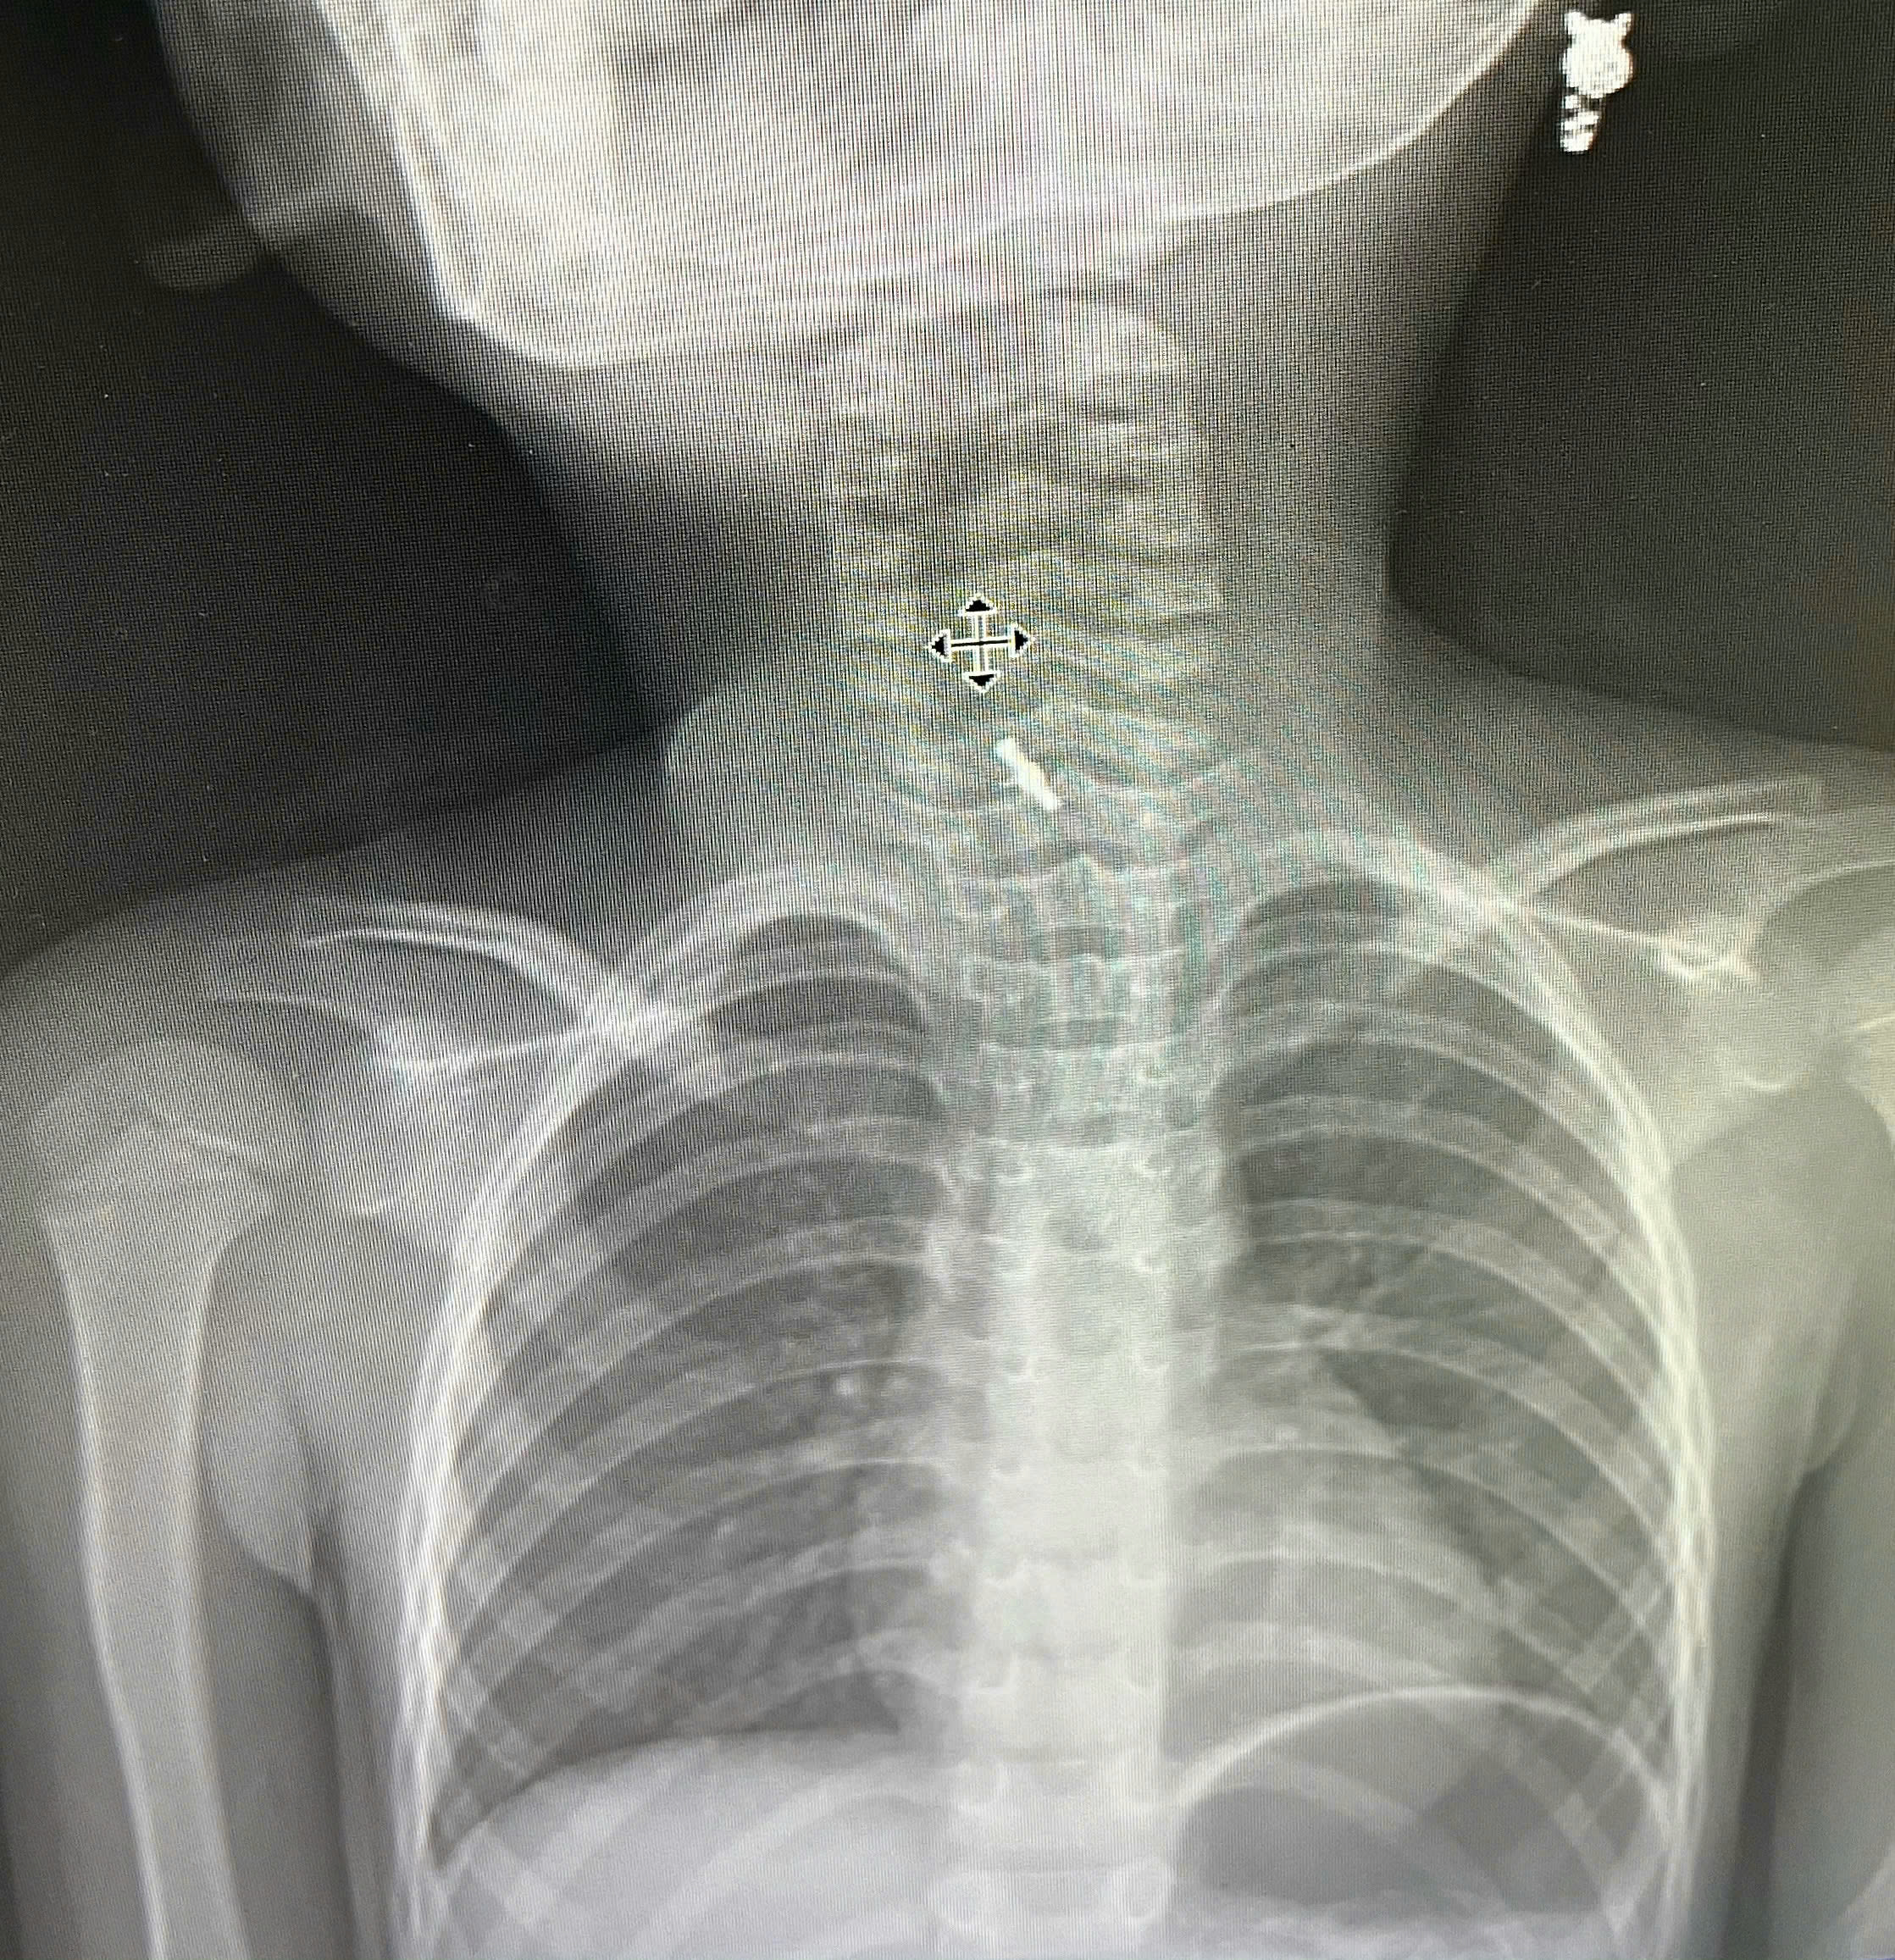

Hình ảnh chụp X-Quang xác định dị vật mắc tại thực quản

Sau thăm khám lâm sàng và chẩn đoán hình ảnh, các bác sĩ tại Bệnh viện Sản Nhi tỉnh Phú Thọ xác định có dị vật mắc tại thực quản. Bệnh nhi nhanh chóng được tiến hành nội soi bằng ống cứng và gắp dị vật ra ngoài. Thủ thuật diễn ra thuận lợi, không gây tổn thương thực quản.